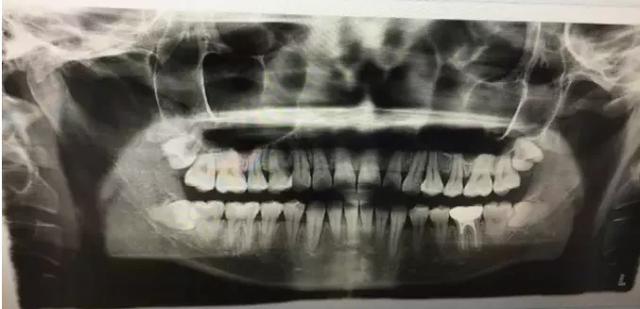

2.侵犯邻牙:通常患者不自知,而由牙医以X光诊断得知。通常智齿萌发的空间不足,而会倒在第二大臼齿上,因而造成第二大臼齿清洁不易,甚至是牙齿部分吸收的现象,造成患者不舒适或牙疼。